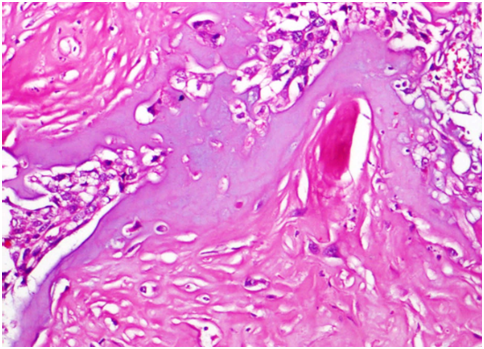

A 41years male patient, presented with a history of swelling over nape of neck for 6 yrs and recent onset of increase in size since 6 months. Patient underwent complete excision. Grossly, mass appeared grey white measuring 1.7cm in diameter. On microscopy, nodules of benign adnexal tumour undergoing malignant transformation (Figure 1) were noted. Benign component is composed of 2 nodules with interwining bands of 2 types of epithelium- inner differentiated cuboidal cells and peripheral undifferentiated cells (Figure 2 & Figure 3). Malignant component was composed of large clear cells with areas of Squamoid (Figure 4) and Chondroid (Figure 5) differentiation, lymph nodes showed metastasis. With all these features, a diagnosis of malignant eccrine spiradenoma with Squamoid and Chondroid differentiation was made.

Figure 5 Areas of chondroid differentiation (X40).